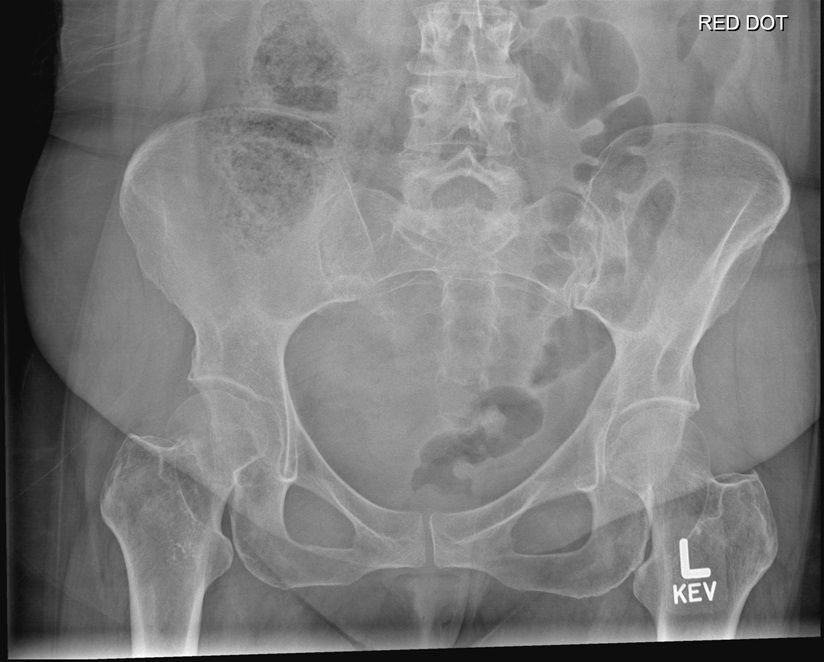

Question 4

Question

Which operation would you perform?

Answer

• THR

• Hemiarthroplasty